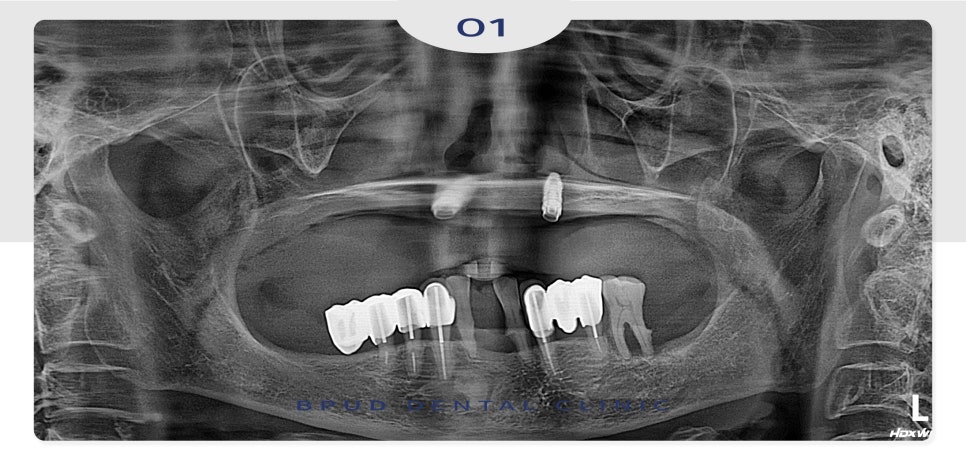

좀 더 정밀한 진단을 위해 3D CT

촬영을 진행하였는데요.

기존 앞니 쪽에 심어져 있는 임플란트 중

하나는 흔들림이 관찰되어 제거를 결정하였고

한 개는 큰 문제가 없어 보이나

사용하기에는 어려움이 있으며

제거 시 치조골 흡수가 일어날 수 있어

잇몸에 묻어두기로 하였습니다.

앞니와 어금니 모두 잇몸뼈가

심하게 흡수되어 1mm도 남지 않아

상악동 거상술과 치조골 이식을 함께

시행하기로 하였습니다.